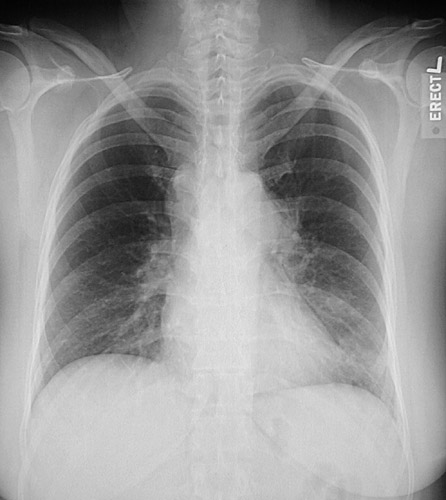

In this example of sarcoidosis, there is prominent hilar and also mediastinal lymphadenopathy. Sarcoidosis is a granulomatous disease of unknown etiology that can lead to interstitial lung disease.